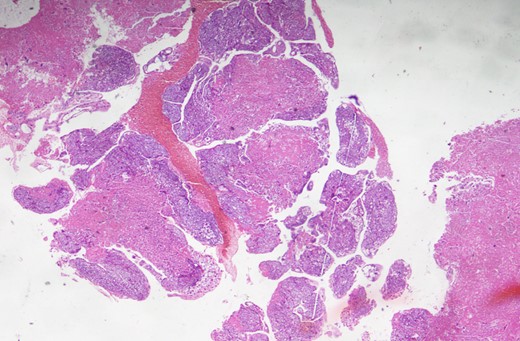

A 25-year-old lady was admitted in the pulmonology ward with the diagnosis of pneumonia. The patient had presented with a history of progressive shortness of breath, chest pain and persistent cough with occasional haemoptysis. She had a history of being treated with antibiotics and anti-TB drugs in outpatient basis. She had had spontaneous abortion 8 months back. Since her symptoms were persistent and her general condition was deteriorating, she was admitted to the ward. On examination, she had crepitations in bilateral chest and an oxygen saturation of only 80%. Chest X-ray showed bilateral infiltrations. CECT chest was done, which revealed pulmonary embolus occluding the main pulmonary artery, and right and left pulmonary arteries (Fig. 1). Venous Doppler did not reveal thrombosis of the lower limbs or IVC. Pulmonary thromboembolectomy was done and embolus (Fig. 2) was sent for histopathological examination. The examination revealed it to be metastatic choriocarcinoma (Fig. 3). Serum beta-human chorionic gonadotrophin (HCG) level was found to be significantly high. CECT pelvis and head were negative for pelvic and CNS metastases. She was managed further with chemotherapy (EMACO regimen) with excellent response to the treatment.